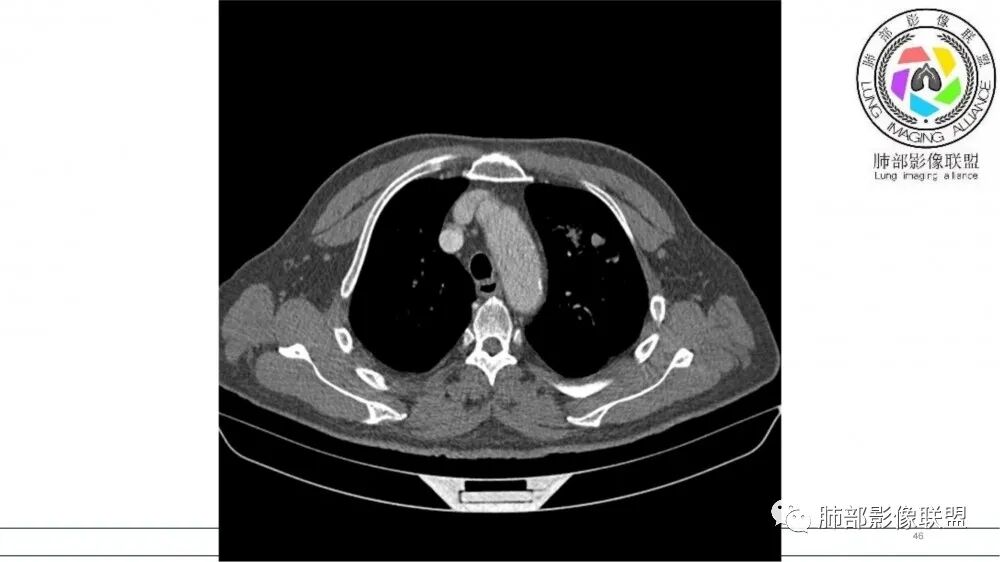

左肺上叶前段支气管杵状指样扩张,内见实性组织阻塞性,并强化明显,边缘饱满,周边多发小斑点影,小花小草征,老年男性,长期吸烟史,方向恶性,首选支气管内浸润鳞Ca可能性大。

左肺上叶前段支气管管壁增厚,腔内软组织填充,有强化,远段阻塞性肺炎,考虑恶性

B3指套征,常规不是鳞癌就是ABPA,有强化丶血管造影征,倾向于鳞癌

进一步查支气管镜,有胸闷,看看嗜酸性粒细胞高不高,查一下曲霉菌特异性ⅠgG丶ⅠgE,总lgE鉴别ABPA

指套征,扩张支气管内软组织强化,远侧肺野阻塞性炎,纵隔、左肺门肿大淋巴结;老年男性,吸烟,考虑鳞癌,鉴别小

2021年8月6日晨读病例结果:小细胞肺癌

指套征:是影像征象,胸部平片表现为手指状密度增高影,以肺门为中心呈放射状分布,CT显示扩张支气管内低密度黏液栓形成或实性病变,呈管状、树枝状或卵圆形密度增高影;支气管扩张伴近端梗阻时,扩张支气管内部黏液分泌物不能排出而形成。可以伴随远端空气潴留征、阻塞性炎症。